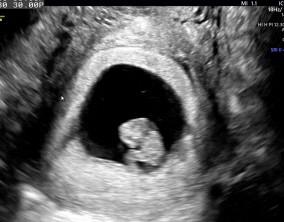

심장소리 이후, 함께 웃게 된 임밍아웃